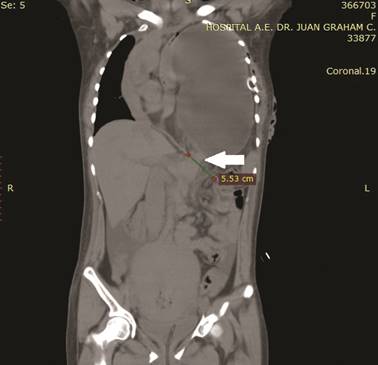

En la TC simple en corte axial, destacó la protrusión del estómago, asas intestinales y grasa mesentérica, a través de un defecto herniario posterior que ocupa hasta un 90% del hemitórax izquierdo, provocando pérdida de volumen del pulmón ipsilateral y atelectasias segmentarias basales derechas (figura 3). En el corte coronal, se identificó un defecto herniario posterior y lateral de aproximadamente 55 mm, además de una importante distensión del estómago, desplazamiento cefálico del bazo y asas intestinales, con compresión y desplazamiento caudal del lóbulo hepático izquierdo (figura 4). Se integró diagnóstico clínico y radiológico de hernia de Bochdalek incarcerada.

Foto: Otorgada por los autores

Figura 4 Tac simple toracoabdominal. Corte Coronal. Defecto diafragmático posterolateral izquierdo de aproximamente 55 mm.